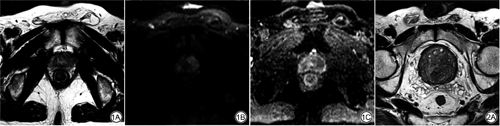

本组51例CGPCa患者中,共检出56个病灶。所有病灶T1WI表现为等信号,T2WI表现为结节状、不规则低信号或稍低信号,边界不清;DCE-MRI扫描显示增强后早期不均匀强化明显,延迟期呈快进快出性强化;DWI上表现为结节状、斑片状高或稍高信号,边界不清,部分病灶已侵犯前纤维基质带或外周带。典型病例图见图1。

本组62例BPH患者中,所有病灶T1WI表现为等信号,T2WI表现为高、低不等混杂信号;DCE-MRI扫描显示增强后早期病灶稍强化,延迟期呈渐进性强化,强化程度无明显下降;DWI上表现大小不等的结节状高低混杂信号或稍高信号,边界较清。典型病例图见图2。